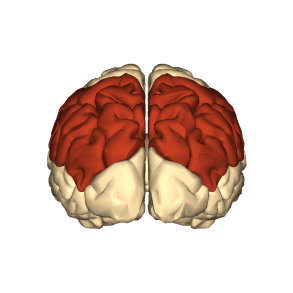

The parietal lobe is the middle part of the brain. It is located behind the central furrow towards the back. It is separated by incision preoccipitalis from the occipital lobe, lying completely posteriorly (1).

As already said, the parietal lobe occupies the upper side of the hemisphere. The parietal lobe limits from the anterior and lateral sides include the area from the front to the central sulcus, from the temporal floor to the lateral sulcus, from the occipital sulcus to the imaginary line that flows from the upper edge of the parietal occipital sulcus to the lower hemisphere edge.

The parietal lobe, like the frontal lobe, forms a significant part of the cerebral hemisphere. In the phylogenetic relationship, it distinguishes the old part - posterior central gyrus, the new part – the upper dark gyrus, and the newest - lower dark gyrus.

Parietal lobe syndrome implies an outbreak of function of this lobe due to damage to its structures. This lobe is located between the frontal lobes in both cerebral hemispheres. The parietal lobe extends from the central sulcus to the parieto-occipital groove separating it from the occipital lobe. It contains the primary somatosensory cortex.

The parietal lobe occupies the upper side of the hemisphere. The function of the parietal lobe is related to the perception and analysis of sensitive stimuli, as well as spatial orientation. Several functional centers are concentrated in the parietal lobe convolutions.